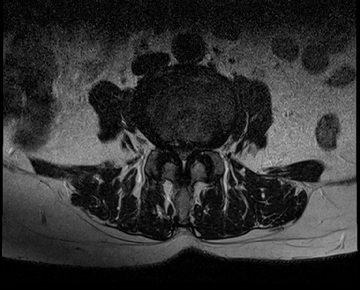

요추 협착증 수술 전·후

2020.08.30

2022.09.06

ㆍ환자 동의를 받은 자료이며, 이미지 사진은 실물과 다를 수 있습니다.

ㆍ모든 자료는 새움병원 자료입니다.